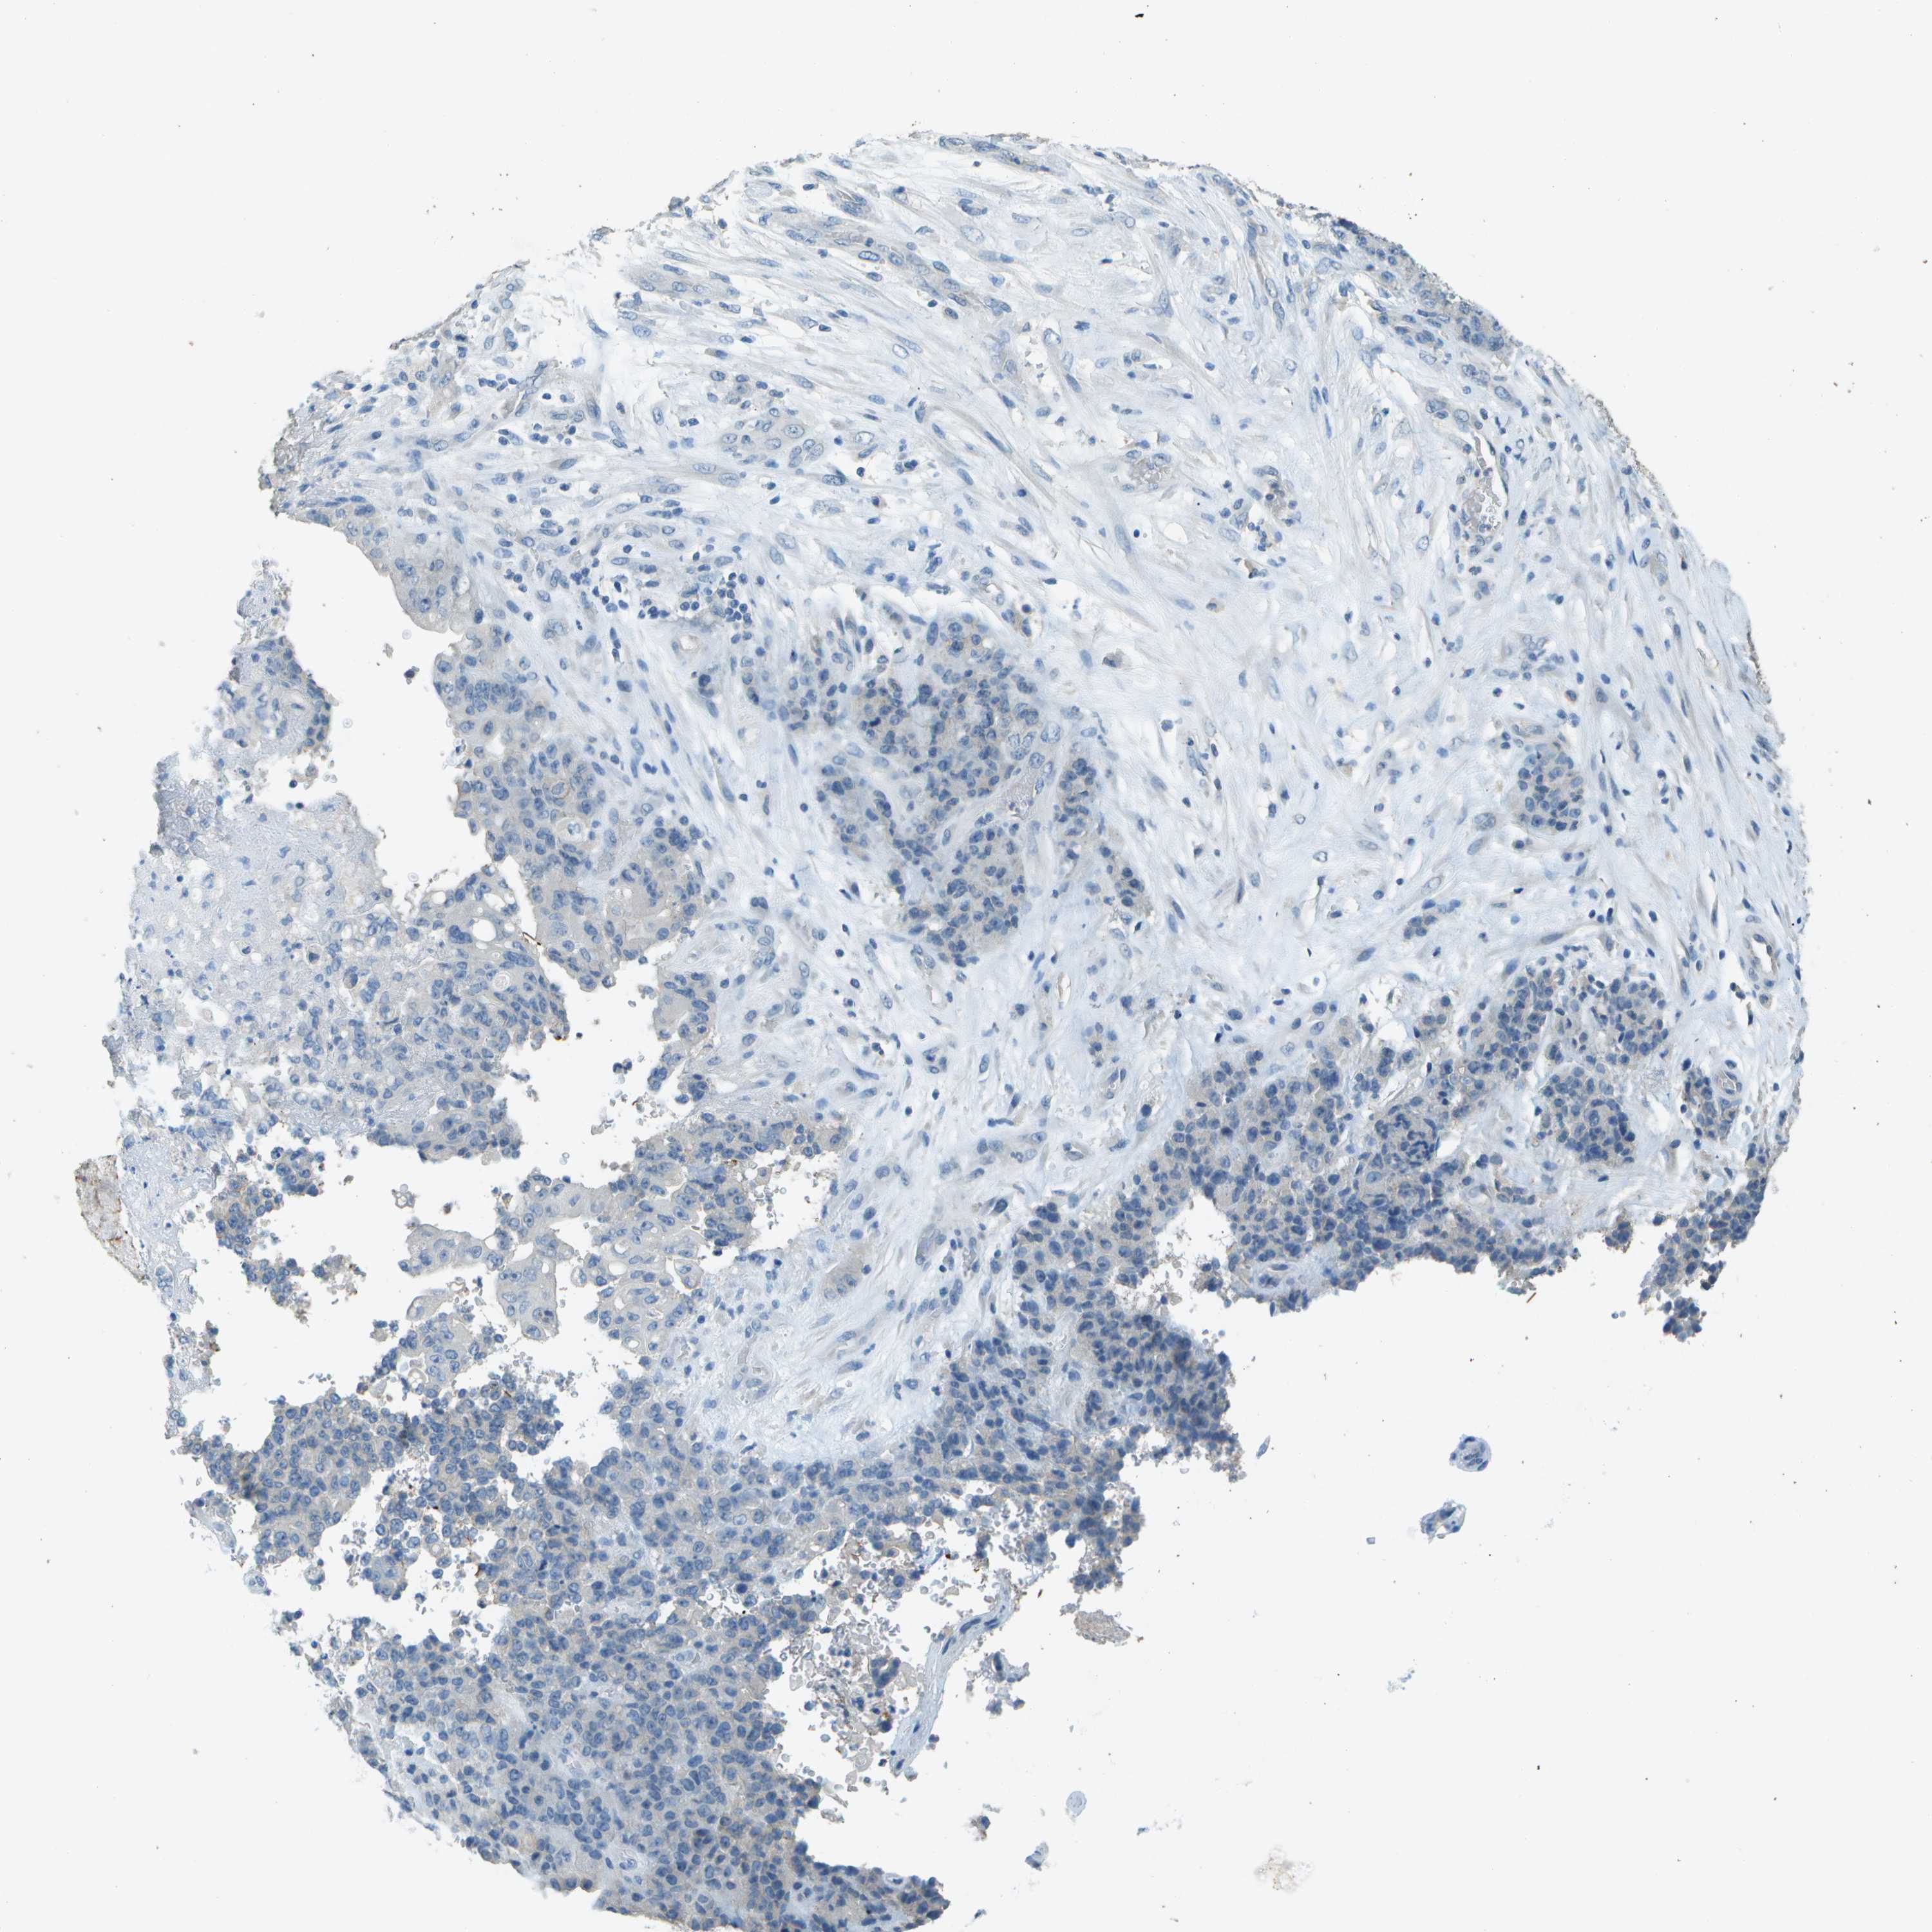

STOMACH CANCER - Protein expressioni

A mouse-over function shows sample information and annotation data. Click on an image to view it in a full screen mode. Samples can be filtered based on level of antibody staining by selecting one or several of the following categories: high, medium, low and not detected. The assay and annotation is described here.

Antibody stainingi

Antibody staining in the annotated cell types in the current human tissue is reported as not detected, low, medium, or high, based on conventional immunohistochemistry profiling in selected tissues. This score is based on the combination of the staining intensity and fraction of stained cells.

Each image is clickable and will lead to virtual microscopy that enables deeper exploration of all samples and also displays staining intensity scores, fraction scores and subcellular localization as well as patient and tissue information for each sample.

Antibody HPA017140

Staining

High

Medium

Low

Not detected

Intensity

Strong

Moderate

Weak

Negative

Quantity

>75%

75%-25%

<25%

None

Location

Nuclear

Cytoplasmic/membranous

Cytoplasmic/membranous,nuclear

Adenocarcinoma, NOS